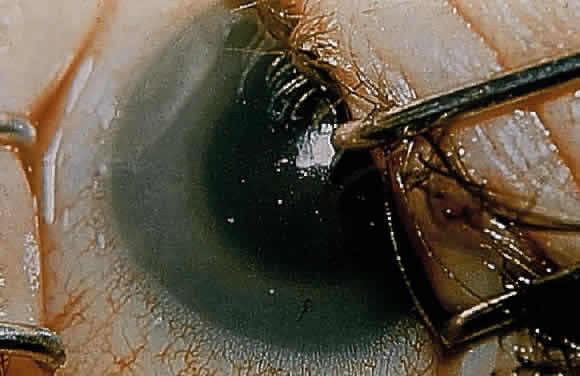

Corneal clouding was recognized early to be an important feature of this disorder, and classic clinical descriptions of the corneal changes are to be found in the older literature.8–12 Clouding of the cornea is usually evident by age 2 to 3 years, often by age 1 year; in some cases it is seen at birth.12,13 Photophobia is a common early symptom. With time there is progression from a generalized haziness or steamy appearance to a dense, milky ground-glass opacification (Fig. 2). On slit-lamp examination, one sees fine granular opacities in the corneal stroma, often increasing in density from the anterior stroma and subepithelial region to the posterior stromal layers.10–12

In 1939, Berliner provided what is probably the first significant histopathologic study of the eye in Hurler syndrome, describing the corneal changes in detail. He found large vacuolated cells under Bowman's layer, fragmentation of Bowman's layer, separation of the corneal lamellae, and deposits of granular material in the stromal spaces.10 Subsequent reports confirmed these findings, and in 1944 Hogan and Cordes noted in addition fine granules in the cytoplasm of the corneal corpuscles.14–16 Later studies documented these histopathologic changes and provided further evidence for mucopolysaccharide accumulation in the cornea.13,17–19 The epithelium may be intact or may show edema and cytoplasmic vacuolization, with accumulation of metachromatic material in and around cells. Bowman's layer usually shows thinning and lamellar splitting or fragmentation, with infiltration of vacuolated cells containing metachromatic material. In the stroma there is swelling and vacuolization of keratocytes, intracellular and extracellular deposition of metachromatic material, and lamellar separation. Descemet's membrane and endothelium usually are described as normal, although cytoplasmic vacuolization and metachromatic staining of the endothelium have been noted. Histochemical techniques provide evidence for mucopolysaccharide accumulation in the vacuolated cells. In their ultrastructural study of the eyes in two cases of MPS IH, Chan and coworkers documented the presence of numerous fibrillogranular inclusions in corneal epithelium, keratocytes, and endothelium, the presence of multimembranous inclusions in keratocytes, and the presence of extracellular fibrillogranular material in corneal stroma.20